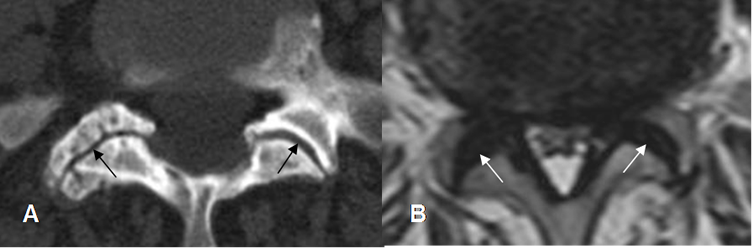

Fig 67. Articulaciones intervertebrales.

A: TAC axial. Hipertrofia de articulaciones interfacetarias, con fenómeno del vacío en el lado derecho.